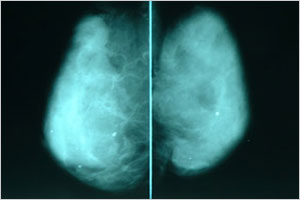

図2 50歳代のマンモグラフィ